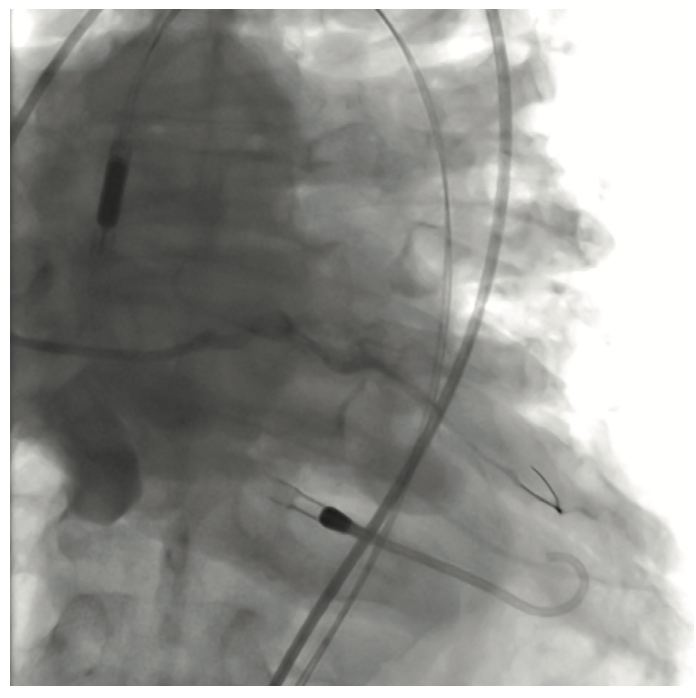

The initial interventional attempt via a transradial approach was unsuccessful due to significant vessel tortuosity. Therefore, a high risk protected PCI was attempted via left femoral access using an Impella 2.5L device (Abiomed) for left ventricular support. The Impella 2.5L was placed via the right femoral access. Before the engagement of coronary arteries, the patient had deteriorated clinically with hypotension and Impella support dropping to 1.4L. Subsequently, the patient went into VT/VF arrest, requiring cardiopulmonary resuscitation (CPR). The patient was emergently intubated. During active CPR and VT storm, selective injections of the left main coronary artery were performed, revealing total thrombotic occlusion of distal left main artery. The patient underwent multiple percutaneous transluminal coronary angioplasties of the left main, ostial and mid LAD, and LCx (OM1) lesions. This was then followed up with stenting of the mid left main into the ostial LAD and LCx (OM1) branch. The coronary interventions were performed during CPR. The patient received a total of 13 defibrillator shocks, and was given intravenous amiodarone and lidocaine pushes during CPR. Return of spontaneous circulation was obtained after 45 minutes. Due to extensive PAD, the Impella device was removed and an intra-aortic balloon pump was placed via a left femoral approach for continued hemodynamic support.